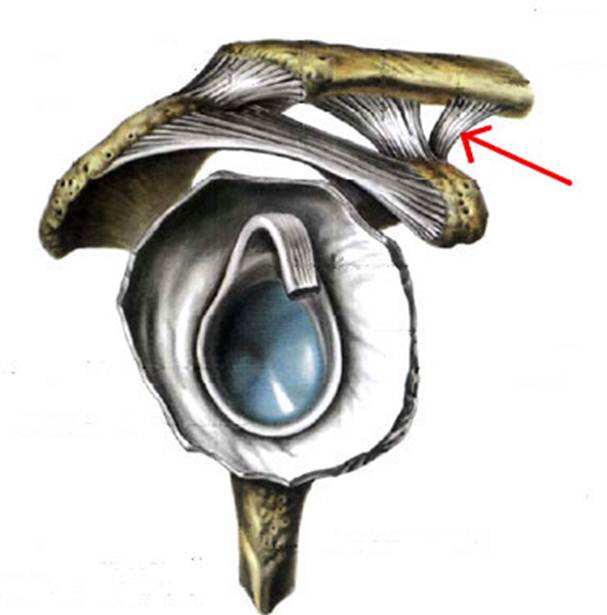

S: Стрелка указывает на art. humeri (латинский язык).

S: Стрелка указывает на lig. coracoclaviculare

S: Стрелка указывает на tendo m bicipitis brachii

S: Стрелка указывает на lig. coracoacromiale

S: Цифрой 6 обозначена суставная капсула плечевого сустава (русский язык).